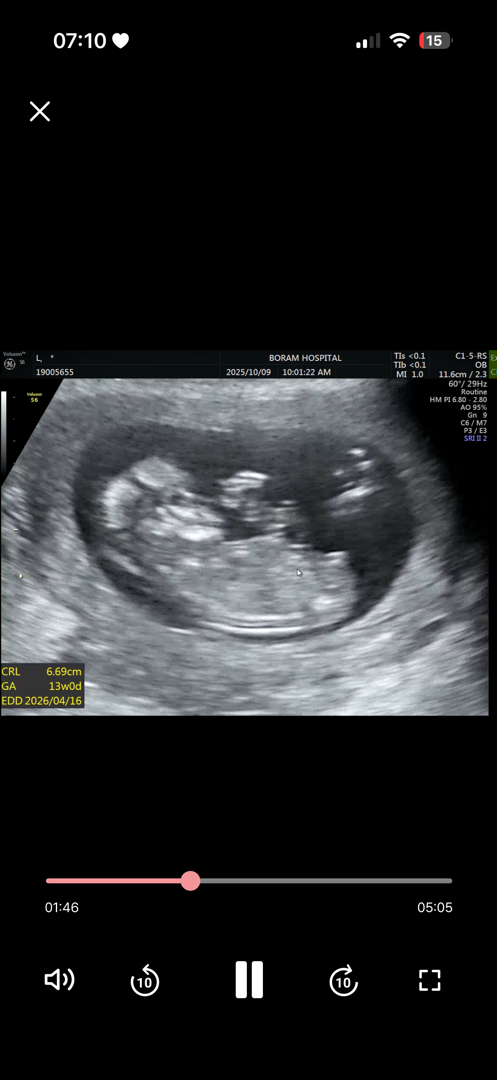

12주3일입니당

ㅠ ㅠ 각도상 어떻게 보이시나요 끝에가 ㄱㅊ라 하기엔 너무 짧지않나요 ... ??? 맘님들은 뭐로 보이시낭ㅎ